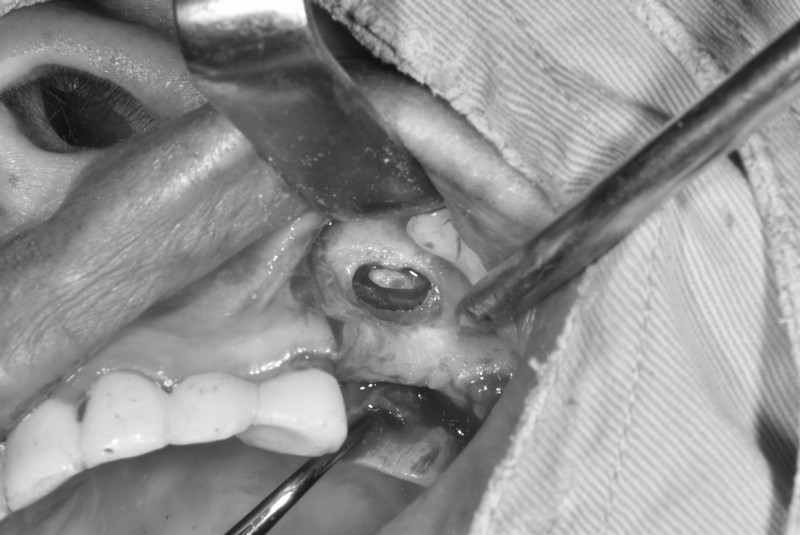

植體周圍炎處理